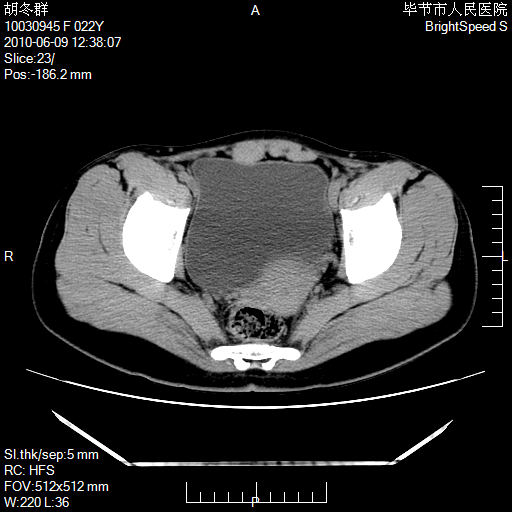

患者23岁,发现腹部包块3月。

左侧卵巢囊腺瘤或囊腺癌

盆腔内囊性占位性病变;考虑左侧卵巢囊腺瘤。

有分隔、壁薄,支持考虑左侧卵巢囊腺瘤。

左侧卵巢浆液性囊腺瘤。

支持考虑左侧卵巢囊腺瘤;宫腔积液。

有分隔、壁薄,支持考虑左侧卵巢囊腺瘤。排尿后,膀胱缩小,由于重力作用,肿块下移就到了膀胱位置,很好理解。